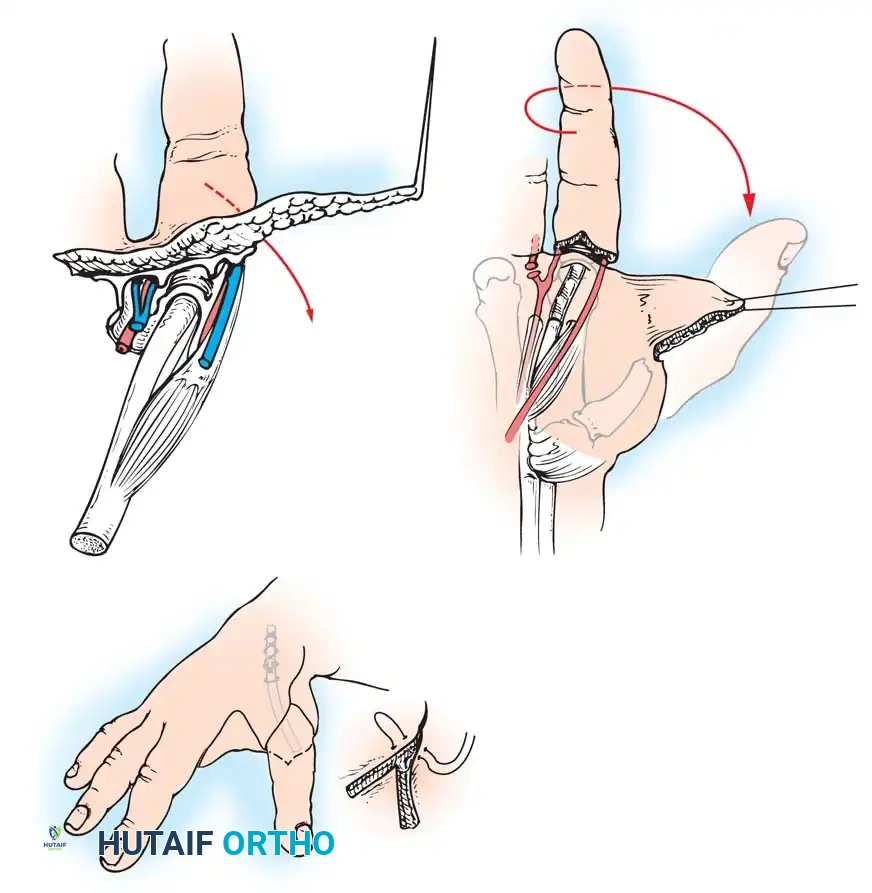

When surgical intervention is indicated, the neuroma must be meticulously dissected free from the surrounding scar bed. The nerve is then placed under gentle traction and sharply divided at a more proximal level, allowing the newly transected end to retract into a healthy, well-padded soft-tissue bed (often deep into a muscle belly or transposed into a drilled bone hole).

An alternative technique involves suturing the radial and ulnar digital nerves end-to-end (centrocentral neurorrhaphy) to create a closed neural loop. While this end-to-end nerve union has been shown to reduce localized tenderness, it does so at the expense of distal touch sensibility and has not been definitively proven to reduce resting pain or cold intolerance compared to standard proximal resection.

- Incision and Flap Design: Make a longitudinal incision on the flexor surface of the forearm, biased slightly toward the radial side. Make a corresponding incision on the dorsal surface, biased toward the ulnar side. On the dorsal surface, elevate a V-shaped flap to form the new web space at the proximal junction of the rays.

- Interosseous Membrane Division: Incise the interosseous membrane longitudinally along its ulnar attachment. Extreme caution must be exercised to preserve the anterior interosseous artery and nerve.

- Osteotomy and Alignment: The radial and ulnar rays should separate 6 to 12 cm at their tips. Motion occurs proximally at the radiohumeral and proximal radioulnar joints. The opposing distal ends of the rays must touch during active closure; if they do not, perform a corrective osteotomy of the radius or ulna.

- Skin Coverage: Excise excess subcutaneous fat. Rotate the skin around each ray and close it so that the suture lines do not lie on the opposing (contact) surfaces of the pincers. Apply split-thickness skin grafts to any remaining defects, ensuring the tactile contact surfaces are covered by sensate, full-thickness skin.

- Closure and Drainage: Suture the dorsal V-flap into the proximal junction to create the web. Insert small rubber drains, obtain meticulous hemostasis after tourniquet deflation, and apply a bulky compression dressing with the rays separated by at least 6 cm.